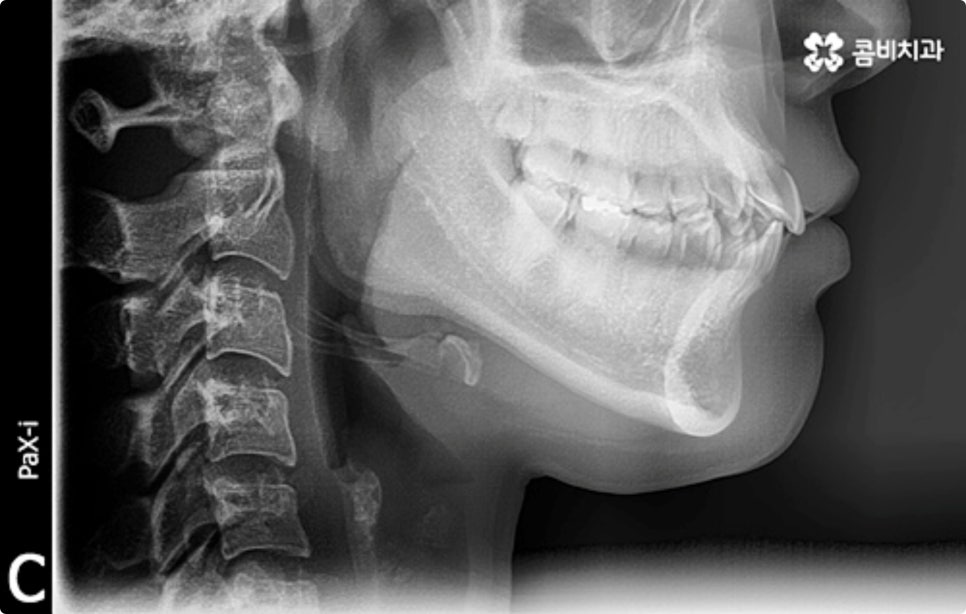

이때 구강 내부는 물론 눈으로 확인하기 어려운 상하악 구조까지 세밀하게 체크하는 3D CT 와 교정 후 모습을 예측하여 보다 안정적으로 교정 플랜을 세울 수 있도록 도와주는 모르페우스 같은 정밀 진단 장비를 갖추고 있는 치과를 찾아 검진을 받는 게 중요한 포인트라고 할 수 있습니다.

클리피씨 교정도 치아 색상의 세라믹 재질을 사용하기 때문에 심미성이 높은 편이지만 만약에 장치가 아예 겉으로 드러나지 않았으면 좋겠다고 생각하신다면 브라켓을 치아 안쪽에 부착하는 설측교정을 이용할 수 있는데요. 하지만 설측교정은 혀와 맞닿는 부분의 이물감, 통증, 발음상 문제 등을 일으킬 수 있기 때문에 잘 보이는 윗니는 설측으로, 잘 드러나지 않는 아랫니는 보통 교정과 같이 순측 (입술쪽) 으로 진행하는 콤비교정을 통해 이를 보완할 수 있어요. 사진에서 살펴보실 수 있는 케이스 역시 이렇게 콤비로 진행한 직장인치아교정 과정으로 시간이 지날수록 점차 치열이 가지런해지고 교합이 올바르게 개선되는 것을 확인해 보실 수 있습니다.